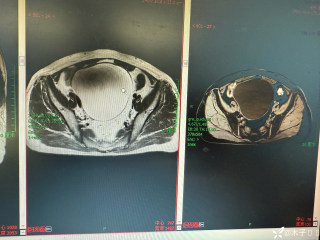

昨天值班遇到的一例晕厥病例,差点漏诊,而最终的解法,始于最简单而质朴的查体。国庆中秋双节的最后一天,8号的早上8点,抢救室床旁晨交班,病人依旧是多而重,交到6床,一个刚入室不久的病人,准备去做CT,夜班医师汇报病史:69岁男性,本次因“头晕伴一过性晕厥1小时”为主诉入抢,1小时前于高铁站因即将赶不上高铁走路快时突发头晕,伴一过性晕厥,约3-4分钟后清醒,清醒后诉今晨未吃早餐,已服用降压药物,仍有头晕头痛、四肢乏力等不适,无胸闷胸痛,无畏寒发热,无咳嗽咳痰,无恶心呕吐,无肢体麻木,无视物模糊等不适,路人拨打120送至我院急诊就诊。既往高血压,长期服用氨氯地平+福辛普利,血压控制一般;糖尿病,长期